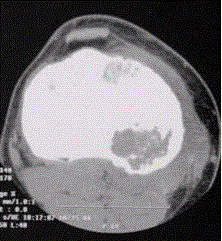

问题 患者男,15岁。右膝X线平片和CT检查见下图。 此病变最可能的诊断是

选项 A.骨巨细胞瘤 B.内生软骨瘤 C.骨结核 D.成软骨细胞瘤 E.软骨黏液样纤维瘤

答案 D